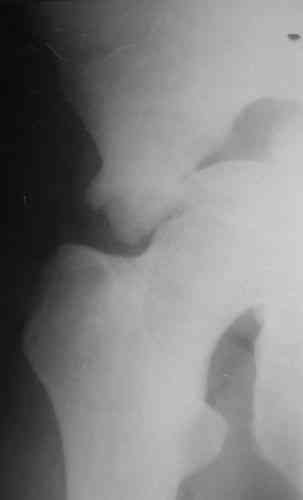

Пациентка 38 лет. В результате ДТП 02.09.06 получила поперечный перелом правой вертлужной впадины, центральный вывих правого бедра, разрыв правого крестцово-подвздошного сустава.

На показанных снимках повреждение правого КПС не очень заметно...

У меня создалось впечатление( одна из РГ), что участок суставной поверхности нагрузочной зоны вертлужной впадины вдавлен( постарайтесь сделать КТ). Если это подтвердиться, то из внутритазового доступа отрепонировать будет невозможно.